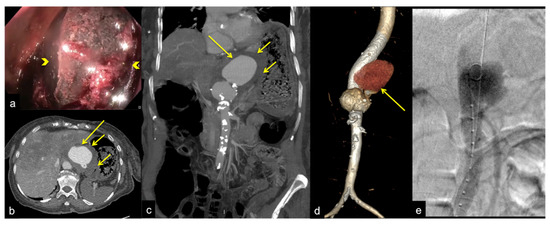

| Aorto-Gastric Fistula (Figure 28) | Copious bleeding. | A connection between the aorta and the gastric lumen. Absence of adipose cleavage planes. |

- Martino, A.; Bennato, R.; Oliva, G.; Pontarelli, A.; Picascia, D.; Romano, L.; Lombardi, G. Primary aortogastric fistula: An extraordinary rare endoscopic finding in the setting of upper gastrointestinal bleeding. Endoscopy 2021, 53, E60–E61. [Google Scholar] [CrossRef]